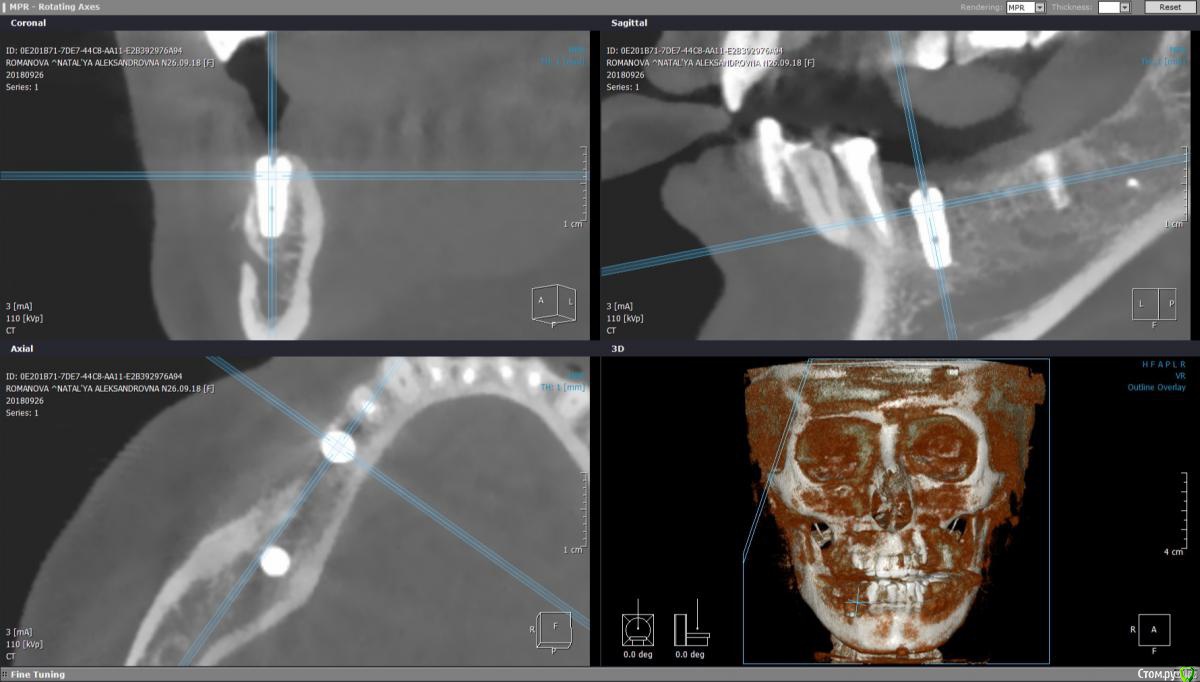

StomV Опубликовано 27 сентября, 2018 Поделиться Опубликовано 27 сентября, 2018 Всех приветствую, подскажите, как бы вы поступили в данной ситуации, все видно на КЛКт собственно, биотип десны тонкий, Варианты: 1.Сделать ССТ.2.Сделать повторно пластику + в дальнейшем сст. ? Пациент не мой достался от предыдущего дока, который уже не работает. Ссылка на комментарий